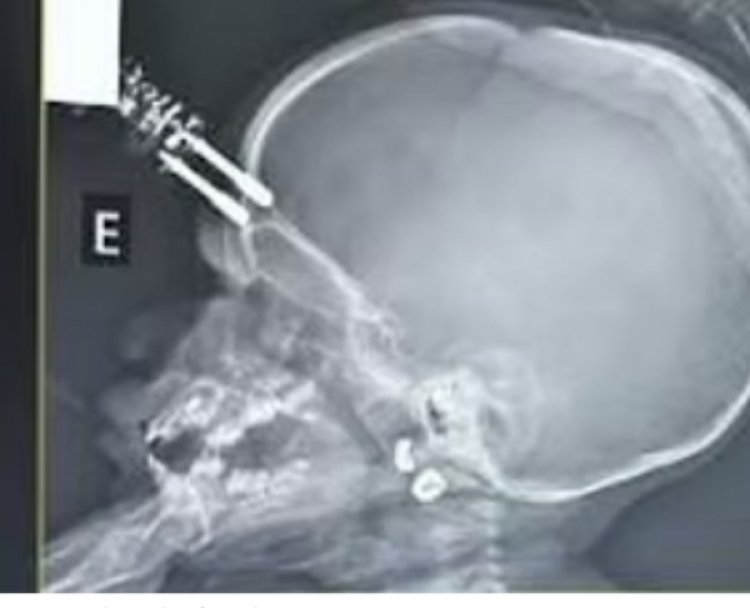

Carregador de celular perfura crânio de bebê de um ano

O caso aconteceu em Divinópolis, onde uma bebê de apenas um ano teve o crânio perfurado por um carregador de celular ao cair da cama. De acordo com os médicos, o carregador atingiu o tecido cerebral da criança e ela precisou passar por uma cirurgia de emergência para retirá-lo.

A mãe encontrou a criança caída no chão, chorando e com sinais de sangramento, e imediatamente a levou para o hospital. A bebê foi submetida a uma cirurgia para remover o carregador e reparar a lesão no crânio. Segundo o neurocirurgião Bruno Castro, o procedimento foi rápido e tranquilo, e a criança acordou bem da anestesia. No entanto, ela precisou permanecer em observação intensiva por 36 horas e recebeu antibióticos para prevenir infecções.

O caso foi atendido no Hospital São João de Deus em Divinópolis, e a recuperação da bebê é considerada positiva pelos médicos.